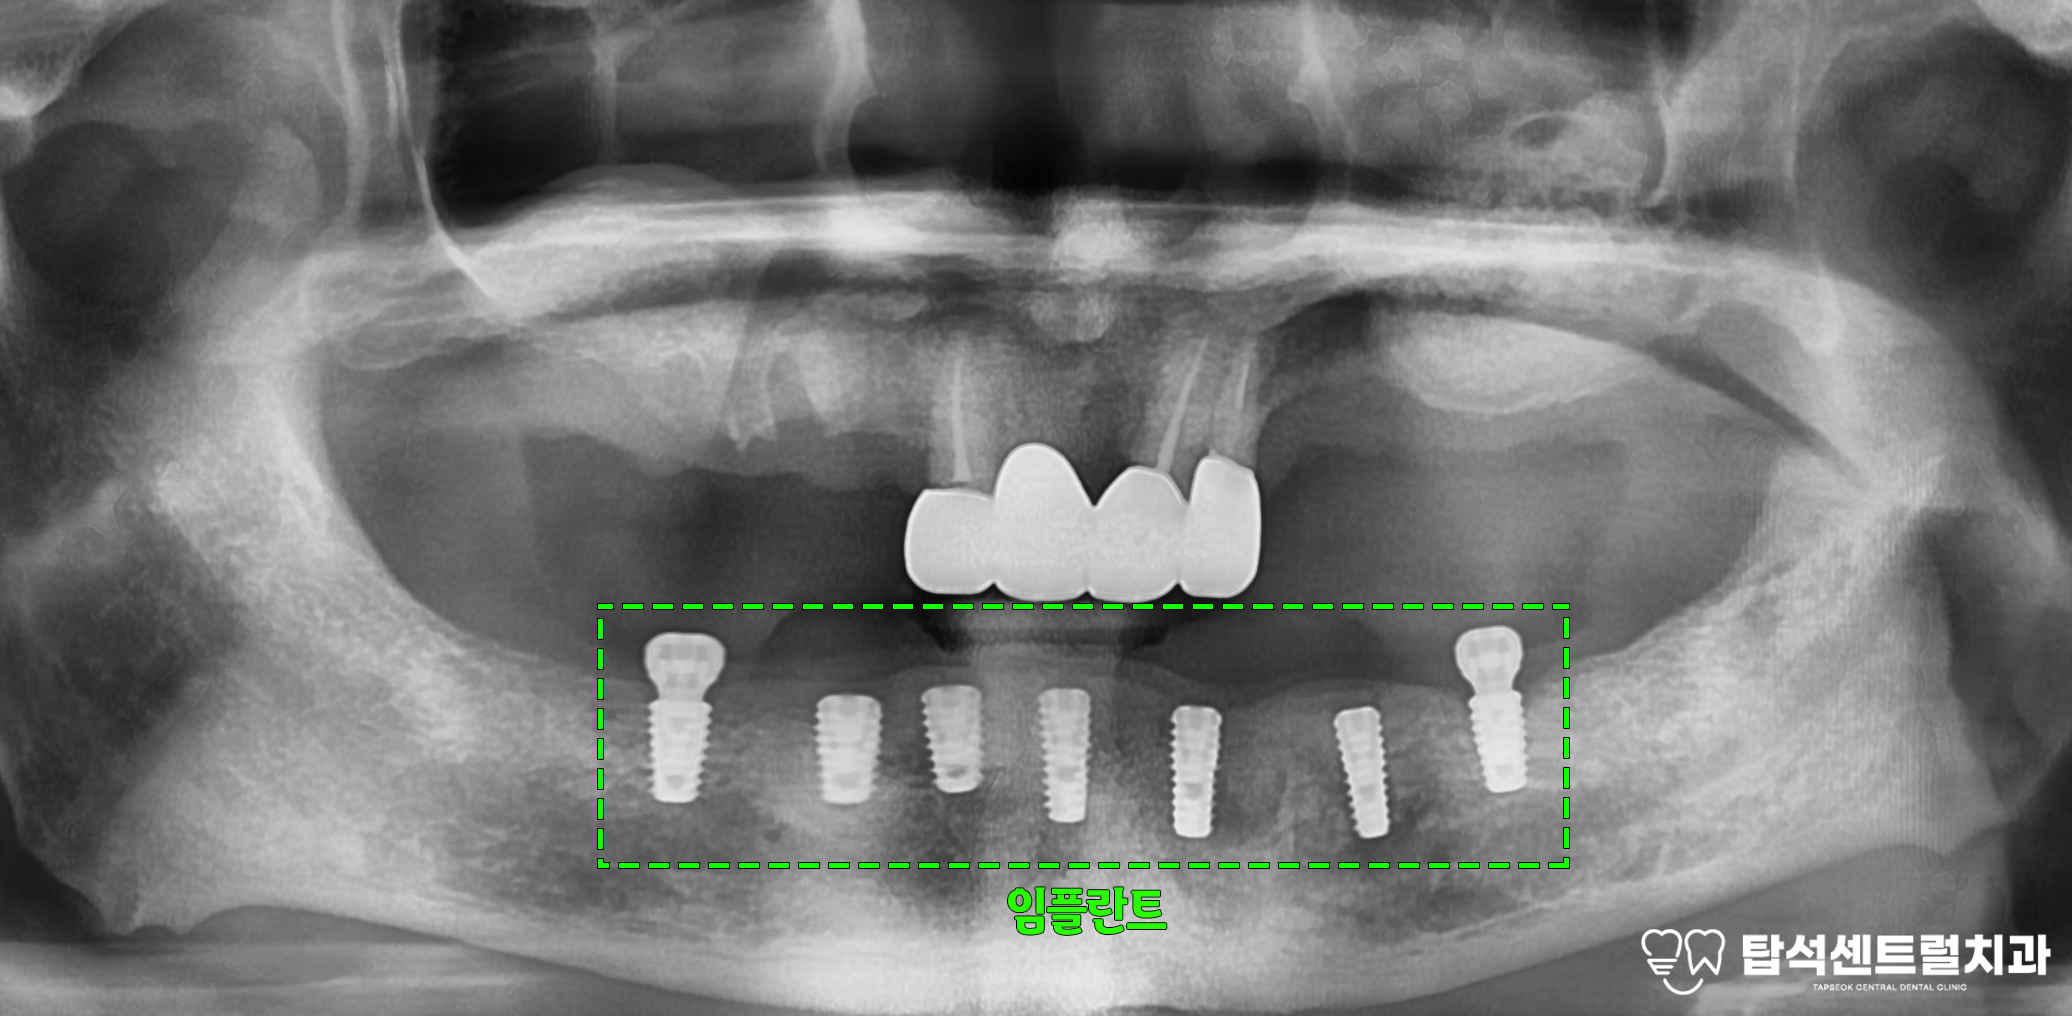

다음은 의정부 치과 에서 촬영한 사진입니다.

위쪽 어금니 부위에

임플란트를 식립할 때

뼈의 높이가 부족한 모습입니다.

의정부 치과 에서 보여드린 사진에서는

위쪽 치아들의 상태가

전반적으로 좋지 않은 것을 알 수 있습니다.

따라서, 여러 치아의 발치가

필요한 경우를 생각해볼 수 있습니다.

아래턱의 경우, 위턱에 비해

상대적으로 골밀도가

높고 골량이 충분합니다.

어금니 부위의 임플란트 식립을

위해 이용 가능한 치조골 높이가

1mm 정도만 남아 있어 뼈가 부족합니다.